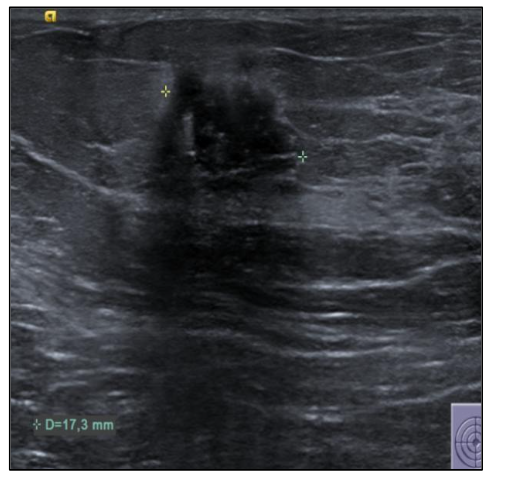

In September 2019, a 69-year-old woman presented to the emergency department of the University Hospital Città della Salute e della Scienza – Turin (Italy), reporting extreme fatigue and dyspnea. She had no comorbidities except for a medical history of papillary thyroid cancer, treated with thyroidectomy and radiotherapy 13 years before. Her complete blood count revealed anemia, thrombocytopenia, and leukocytosis (Hb: 7.8 g/dL, PLT: 37 × 109/L, WBC: 45 × 109/L), while her physical examination was normal. The bone marrow smear showed 84% of blasts with myeloid immunophenotype (CD45, CD13, CD33, HLA-DR, lysozyme, CD36, CD64, CD11bc, partial CD14, and CD4 positive), molecular biology showed NPM1 mutation and FLT3-ITD positivity, while karyotype was normal (46, XX, 20/20). Consequently, a diagnosis of FLT3-ITD+ and NPM1 mutated t-AML was made. Induction chemotherapy was started with CPX-351 (liposomal daunorubicin 44 mg/m2 and cytarabine 100 mg/m2), obtaining CR with a 3-log NPM1 reduction (0.177). She was consolidated with CPX-351 (liposomal daunorubicin 29 mg/m2 and cytarabine 65 mg/m2 day 1 and 3), remaining in CR with persistent low level of measurable residual disease (MRD), NPM1 0.34. Meanwhile, we found a suitable HLA matched donor, but the patient refused the transplant procedure. Thus, we decided to start off-label azacitidine as maintenance therapy (50 mg/m2 subcutaneous daily for 5 days, every 28 days). Maintenance therapy was globally well tolerated, and the patient experienced only positivity for COVID-19 without need of hospitalization or additional care. She remained in CR with persistent MRD in BM (NPM1 0.044 after 12 cycles). During the fifteen course (May 2021), we found a palpable right mammary nodule on physical examination, confirmed on ultrasound, with a diameter of 18 x 11 mm.

We stopped azacitidine and we promptly biopsied the nodule with a diagnosis of breast infiltration by AML blasts carrying the NPM1 mutation. CT scan and PET of chest, neck and abdomen were negative, and BM evaluation showed 1% blasts, with NPM1 0.044. The FLT3-ITD mutation resulted positive on breast cells while negative on medullary blasts. Thus, concluding for extramedullary relapse of AML FLT3-ITD mutated, we decided to start gilteritinib as single agent, at a dose of 120 mg daily. After 30 days, mammary ultrasound showed a reduction in diameter of the nodule.

In 4 months, the lesion has completely disappeared. The PET scan performed after 5 months of treatment was persistently negative and confirmed the absence of other uptakes. BM re-evaluation showed no blasts, with NPM1 0.006. Today, after 44 months of treatment, our patient is still in CR without signs of clinical and radiologic relapse.